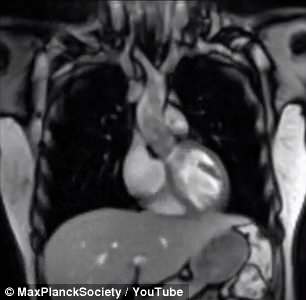

最近发表的一项研究指出,对喝醉状态和清醒状态的受试者的核磁共振扫描结果显示,他们的前额叶皮质出现了与酒精有关的变化。该脑区本应负责调控社交行为和进攻行为,也许醉酒后的怒气也与之有关。

核磁共振扫描结果显示,在做出攻击性反应时,喝醉的受试者大脑前额叶皮质的脑部活动明显少于未喝醉的受试者。更具体而言,受试者喝醉时,前额叶皮质的背内侧和背外侧脑部活动减少,而这两块脑区恰好与短期记忆和抑制力有关。